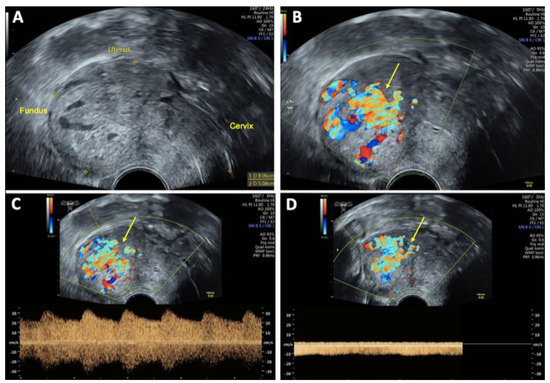

On vaginal examination, no abnormalities or active bleeding were observed. Transvaginal ultrasound revealed a retroflexed uterus measuring 81 × 51 mm, with a suspicious, irregular, hypoechoic, hypervascular lesion measuring 40 × 34 mm on the posterolateral wall of the uterus. This lesion appeared as a prominent vascular tangle extending toward the uterine cavity. Color Doppler sonography demonstrated high-velocity blood flow within the lesion, with a peak systolic velocity (PSV) of 0.3 m/s and a low-resistance pattern, indicated by a resistance index (RI) of 0.43. Distinct arterial and venous blood flow patterns were clearly visualized within the suspicious area (Figure 1 and Figure 2). Both ovaries exhibited normal physiological morphology, appearance, size, and follicle count without abnormalities.

Figure 1. Transvaginal sonography (TVS) Imaging of uterine arteriovenous malformation (AVM): (A) 2D TVS demonstrating a retroflected, enlarged uterus measuring 81 × 51 mm with an inhomogeneous structure in the uterine cavity and fundus; (B) 2D TVS with color Doppler revealing a vascular tangle suggestive of an AVM (arrow); (C) 2D TVS with color Doppler illustrating arterial blood flow within the lesion; (D) 2D TVS with color Doppler depicting venous blood flow in the affected area.